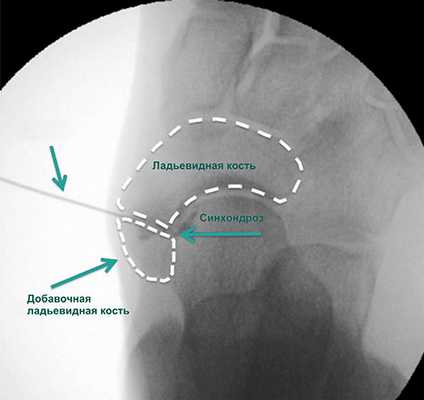

Инъекционная терапия

Введение в области синхондроза ладьевидной кости лекарственных препаратов при острых воспалительных явлениях в этой области осуществляется под лучевым контролем и в условиях кратковременной общей анестезии. Оно помогает подтвердить диагноз и купировать воспалительные явления.

Такое лечение может на некоторое время уменьшить выраженность симптомов, а иногда полностью избавить от них пациента, однако оно никак не может повлиять на те или иные существующие деформации стопы.

Правильность положения иглы подтверждается введением рентгенконтрастного препарата